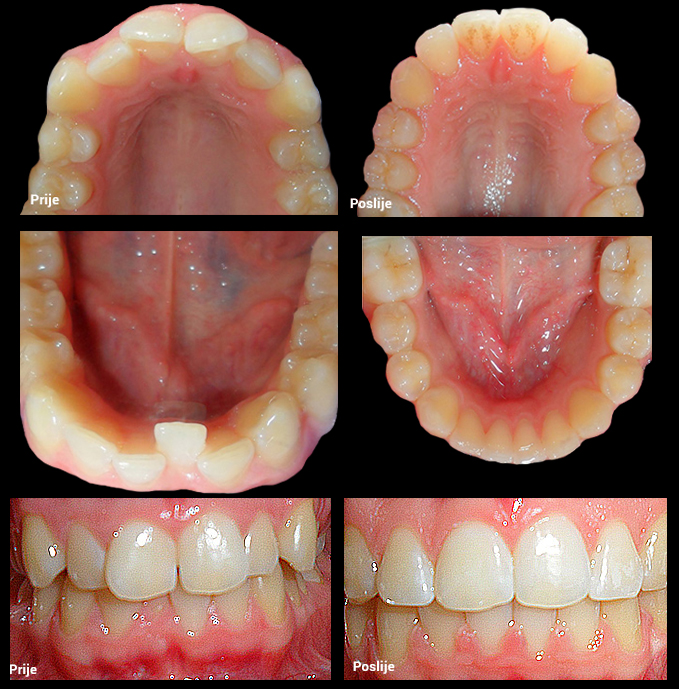

O našoj kvaliteti najbolje govore naši rezultati!